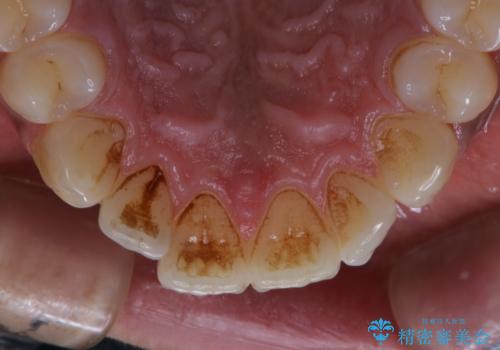

- 電子タバコを吸う習慣があり、ステインがついてしまっている見た目が気になるとのことで来院されました。ステインだけではなく、歯石も全体的に付着していたためPMTC60分コースを行いました。

PMTCは、歯に付着した汚れを除去していくため、着色が気になる場合にも行うことができます。ご自身でのセルフケアだけで着色を落とそうとすると、逆に歯を傷つけてしまったり、精密に汚れを除去できないこともあります。また、日常生活で着色しやすい飲食物を避けたりすることはストレスに感じてしまったり、あまり現実的ではありません。